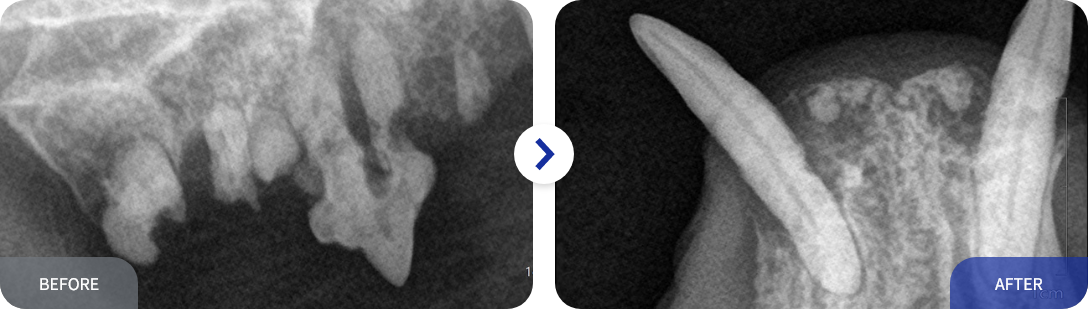

치과 방사선은 촬영은 치과 치료의 시작입니다.

눈으로 보이는 치아의 부분은 치아의 아주 일부분입니다.

치아 뿌리, 치조골의 상태는 치과 방사선만으로 확인이 가능합니다.